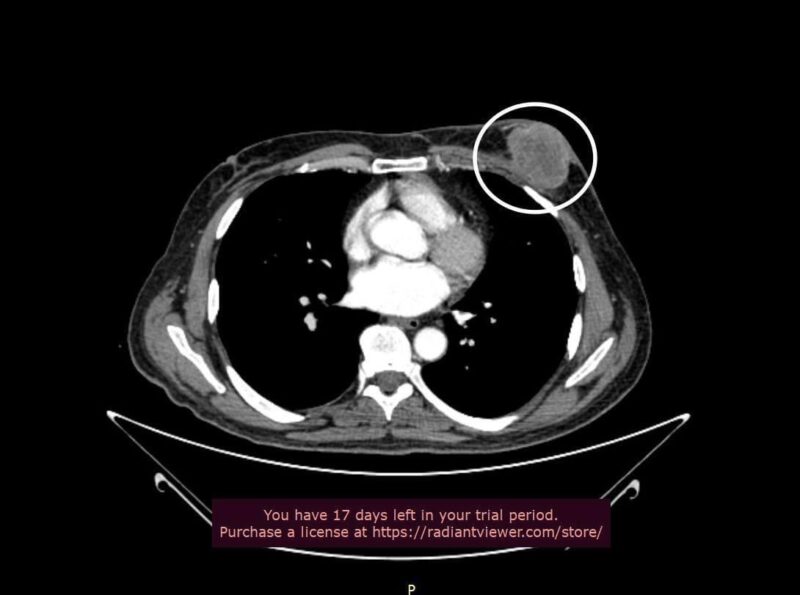

Діагноз, який виявили медики після проведення УЗД та КТ-обстеження, приголомшив пана Ореста! У нього виявили рак молочної залози. У чоловіків така недуга зустрічається в 100 разів рідше за жінок.

Ба більше – пухлина, яка сягала 8 сантиметрів, уже почала розпадатися. Часу на зволікання не було. Оперувати треба було якнайшвидше. Як саме – радилася мультидисциплінарна команда з мамологів, онко- та реконструктивних хірургів. Вирішили оперувати в два етапи. Спершу свою частину роботи мали виконати онкологи.